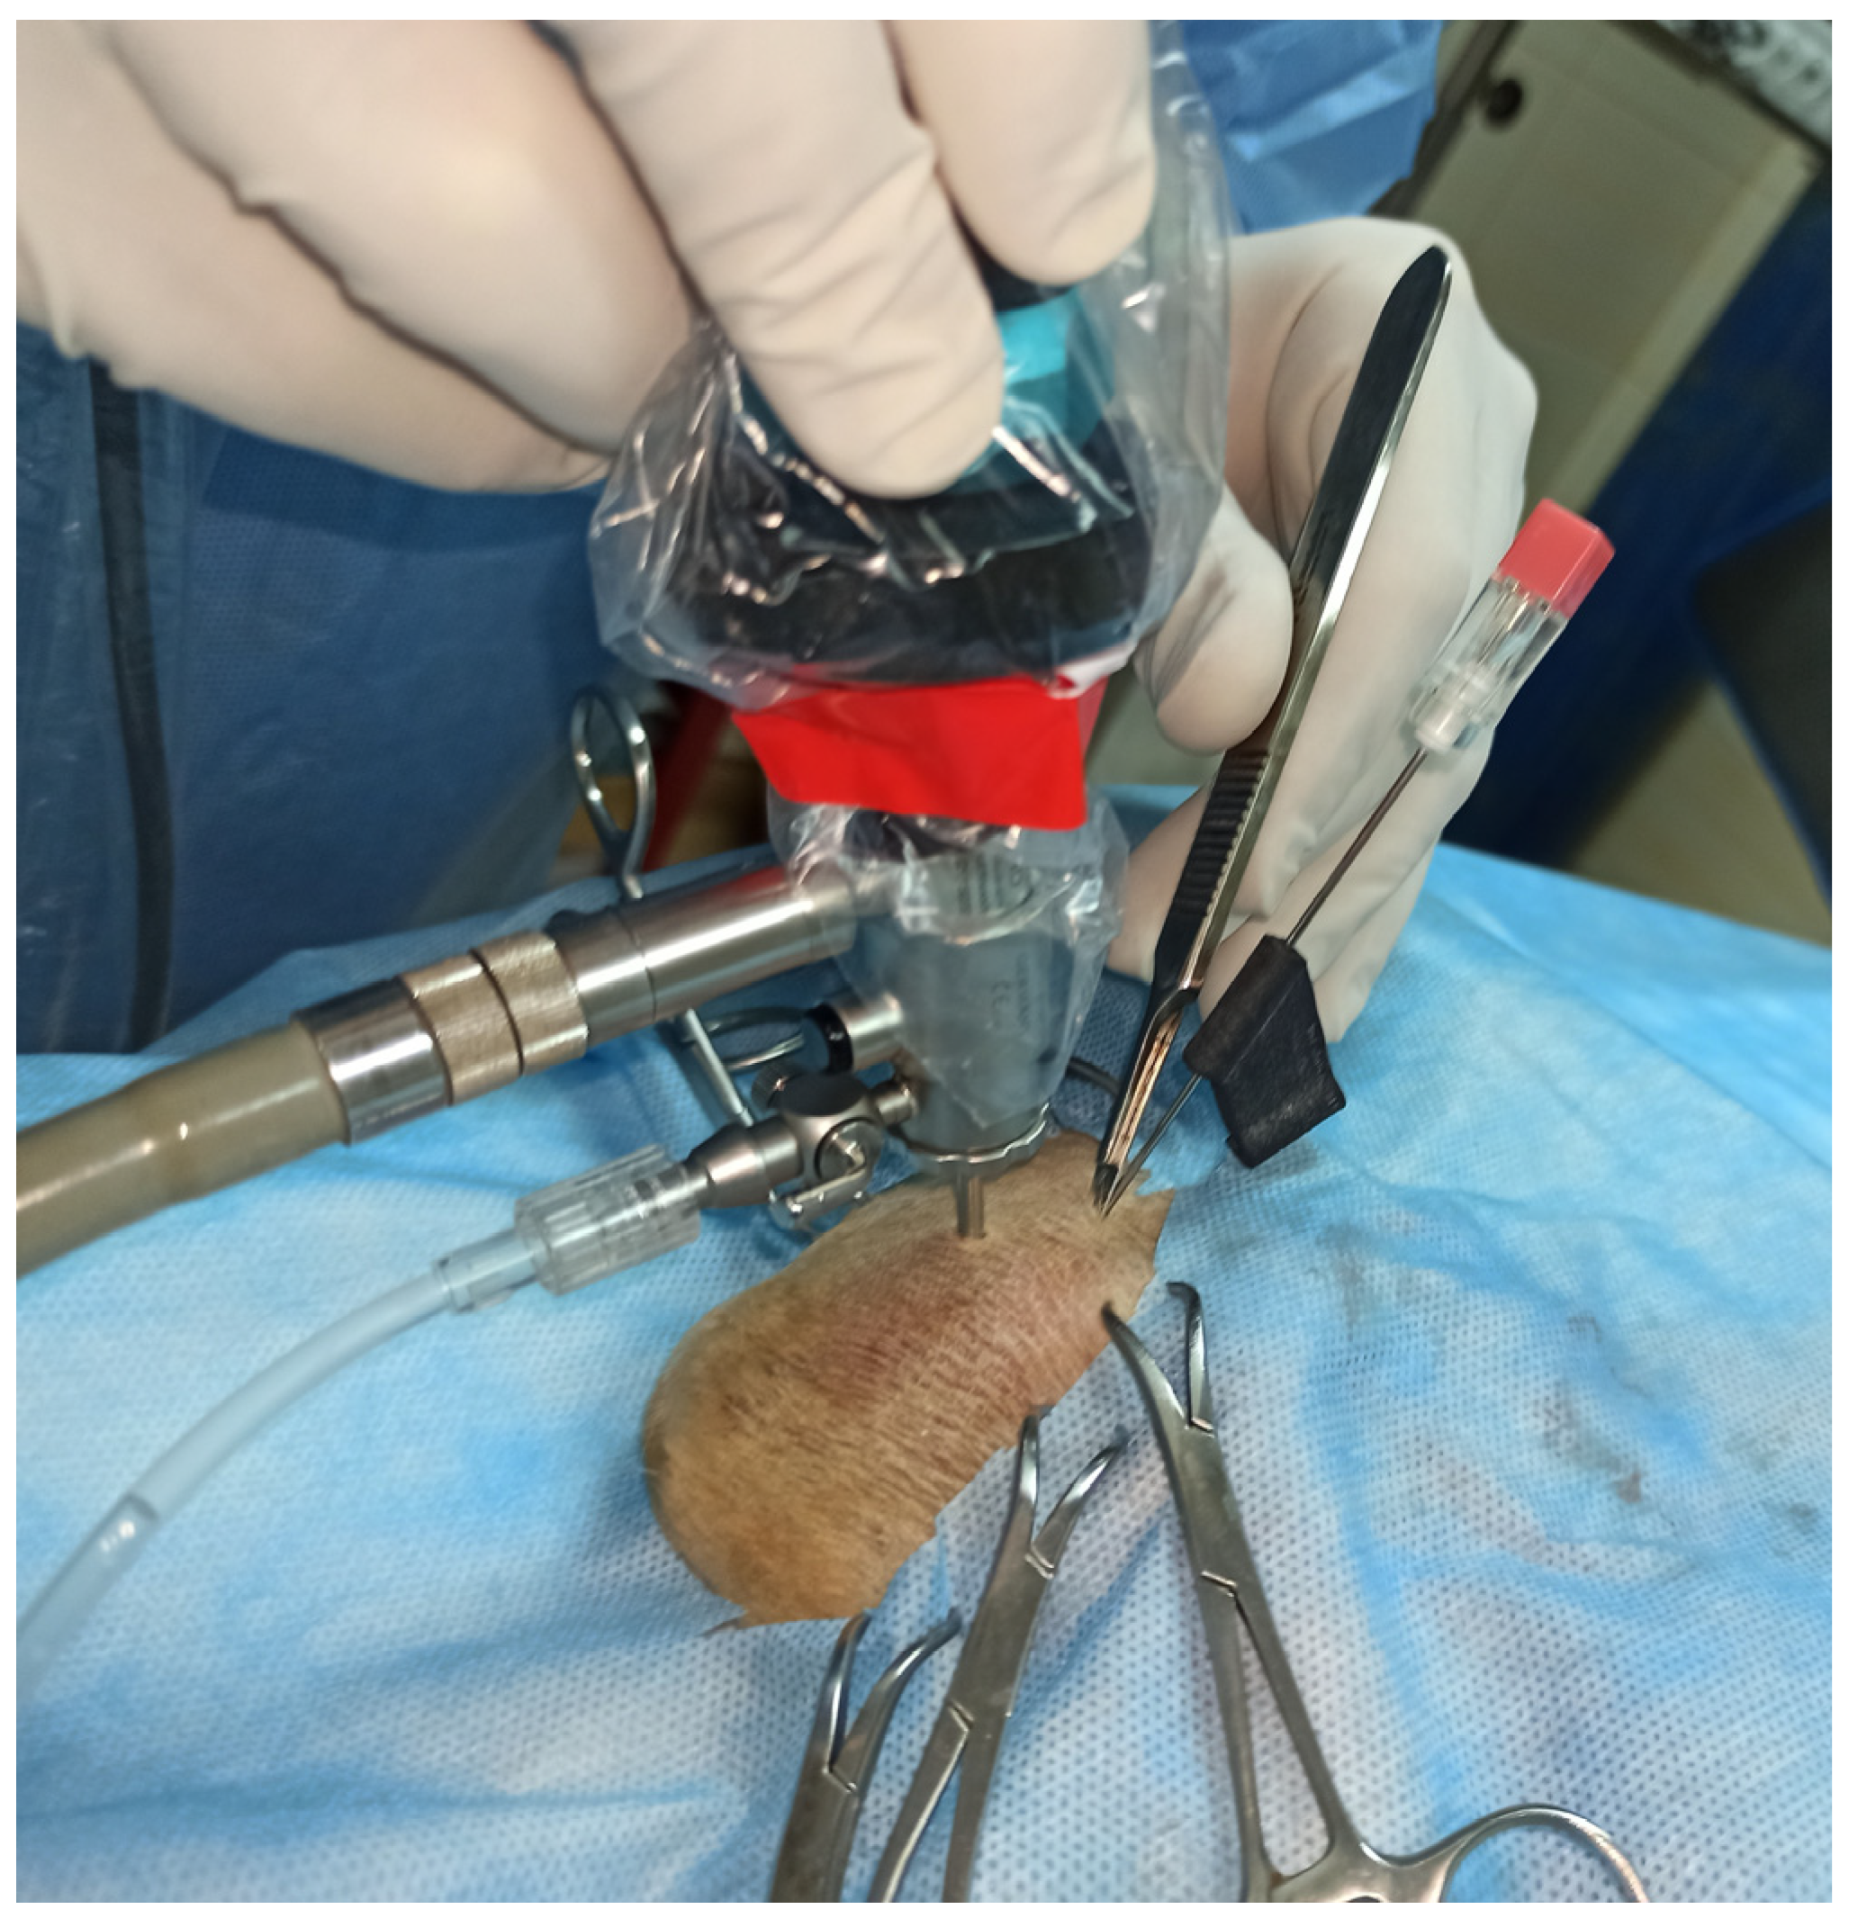

2. Materials and Methods

2.2. Cadaver Studies

3.2. Cadaver Studies